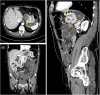

Adult patients comprise 5% of all intussusceptions with 2 to 3 cases per million per year. Of those, only 10% of adult intussusceptions involve the stomach. Gastrogastric intussusceptions are most often associated with lead points caused by gastric neoplasms, with a few caused by hiatal hernias or ascites. Unlike children, adult intussusceptions are rarely idiopathic. Herein, a case is presented of a 65-year-old male who was found to have a gastrogastric intussusception in the setting of a small bowel obstruction with no evidence of neoplasm confirmed by biopsy. The patient initially presented to the emergency department with nausea, emesis, and epigastric pain. Given that almost all reported cases have been associated with gastric neoplasms, this case shows an unusual phenomenon of gastrogastric intussusception that has not reported before. Furthermore, our case offers a different etiology of gastrogastric intussusception in adults other than being due to a gastric neoplasm.